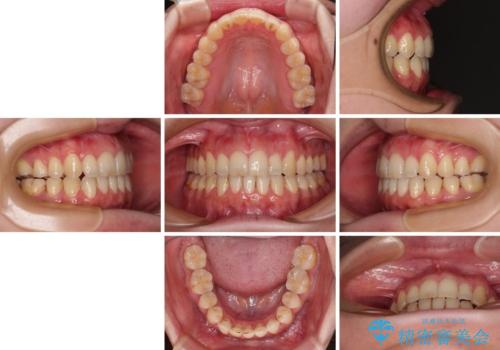

- 1年6ヶ月

クロスバイトはワイヤー矯正が得意とするところであり、上下前歯の非接触や開咬はインビザラインの得意とするところであるので、ワイヤー装置により事前にクロスバイトを改善し、その後にインビザラインにて仕上げていくこととしました。

奥歯の咬み合わせに問題がある場合、インビザラインでは改善できないことが多々あります。事前にワイヤー装置により問題点を解消しておくことで、スムーズにインビザラインでの矯正治療を進めていくことができます。